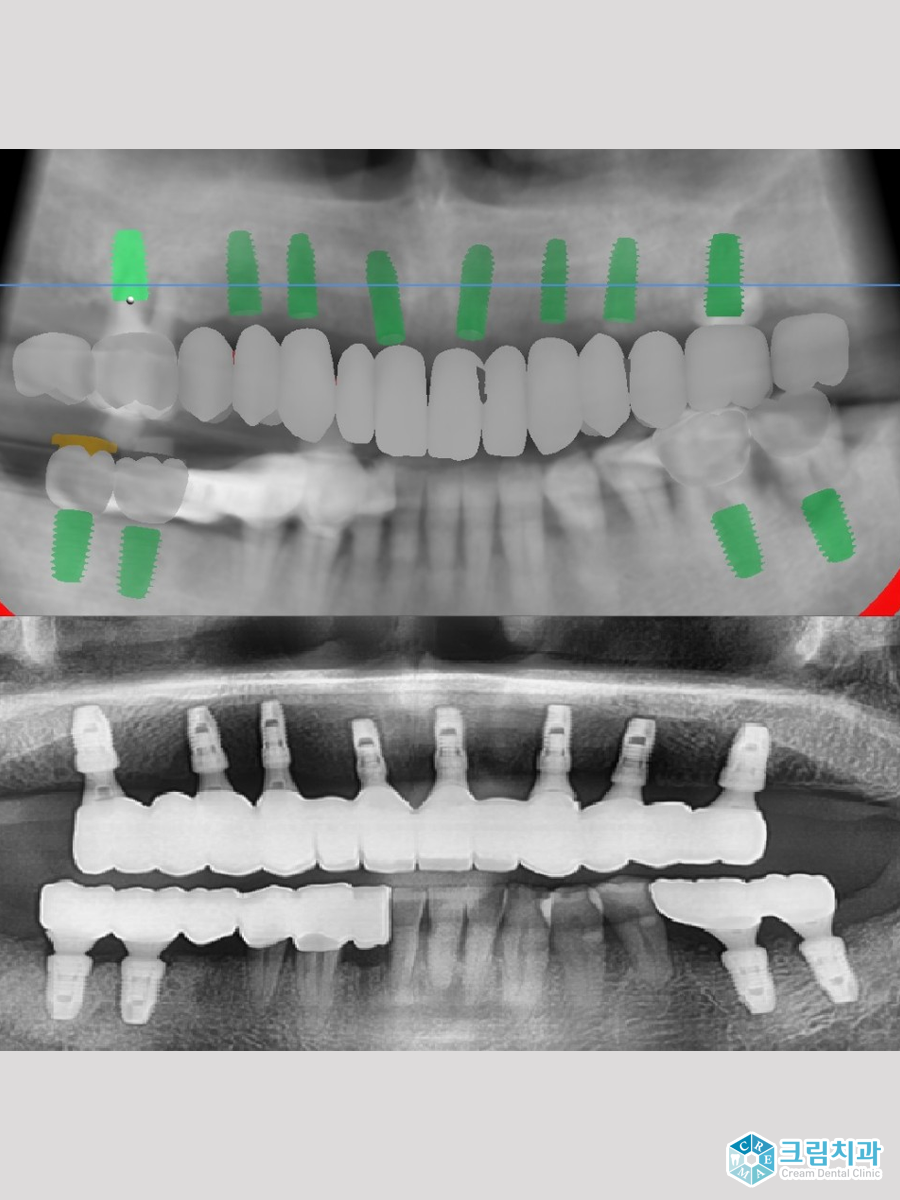

실제로 환자분들의 수술 과정과 후 사진을 비교해보면 계획에서의 식립 위치와 실제 임플란트가 심어진 X-레이 사진에서의 위치가 동일한 걸 확인할 수 있습니다.

때문에 잘못된 임플란트 식립이나 무리한 보철물로 인해 발생할 수 있는 임플란트 피로도가 많이 감소하는 것도 네비게이션 임플란트의 장점입니다. 자연히 임플란트의 기대수명 또한 늘어나겠죠.